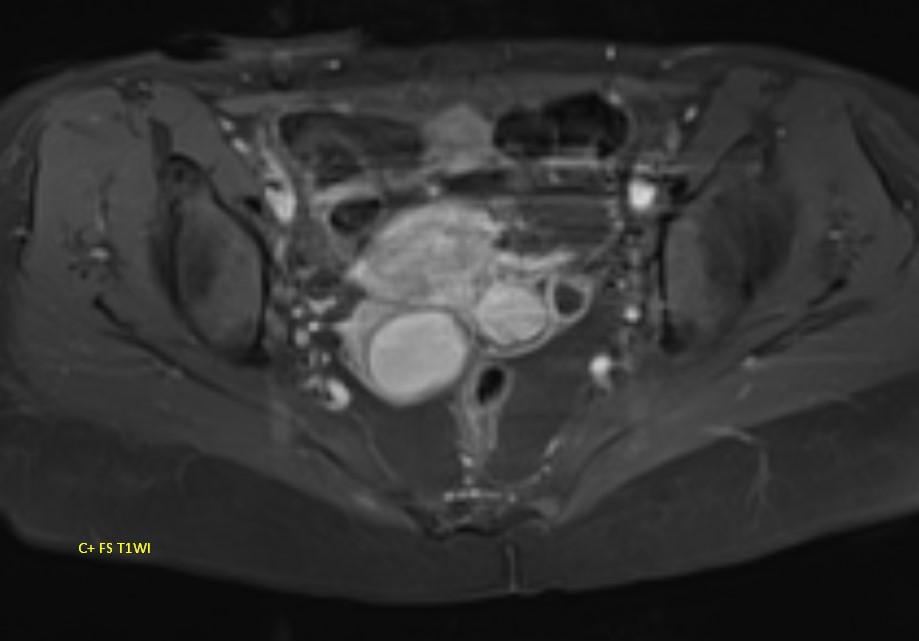

*23-year-old female with primary infertility.

Answer: Kissing Ovary Sign

MR images demonstrating the kissing ovaries, bilateral endometriomas (chocolate cysts), and peritoneal inclusion cyst (peritoneal pseudocyst).

Blood products in ovaries may cause adhesions to pull the ovaries toward the midline. This is considered a sign of pelvic endometriosis (1).